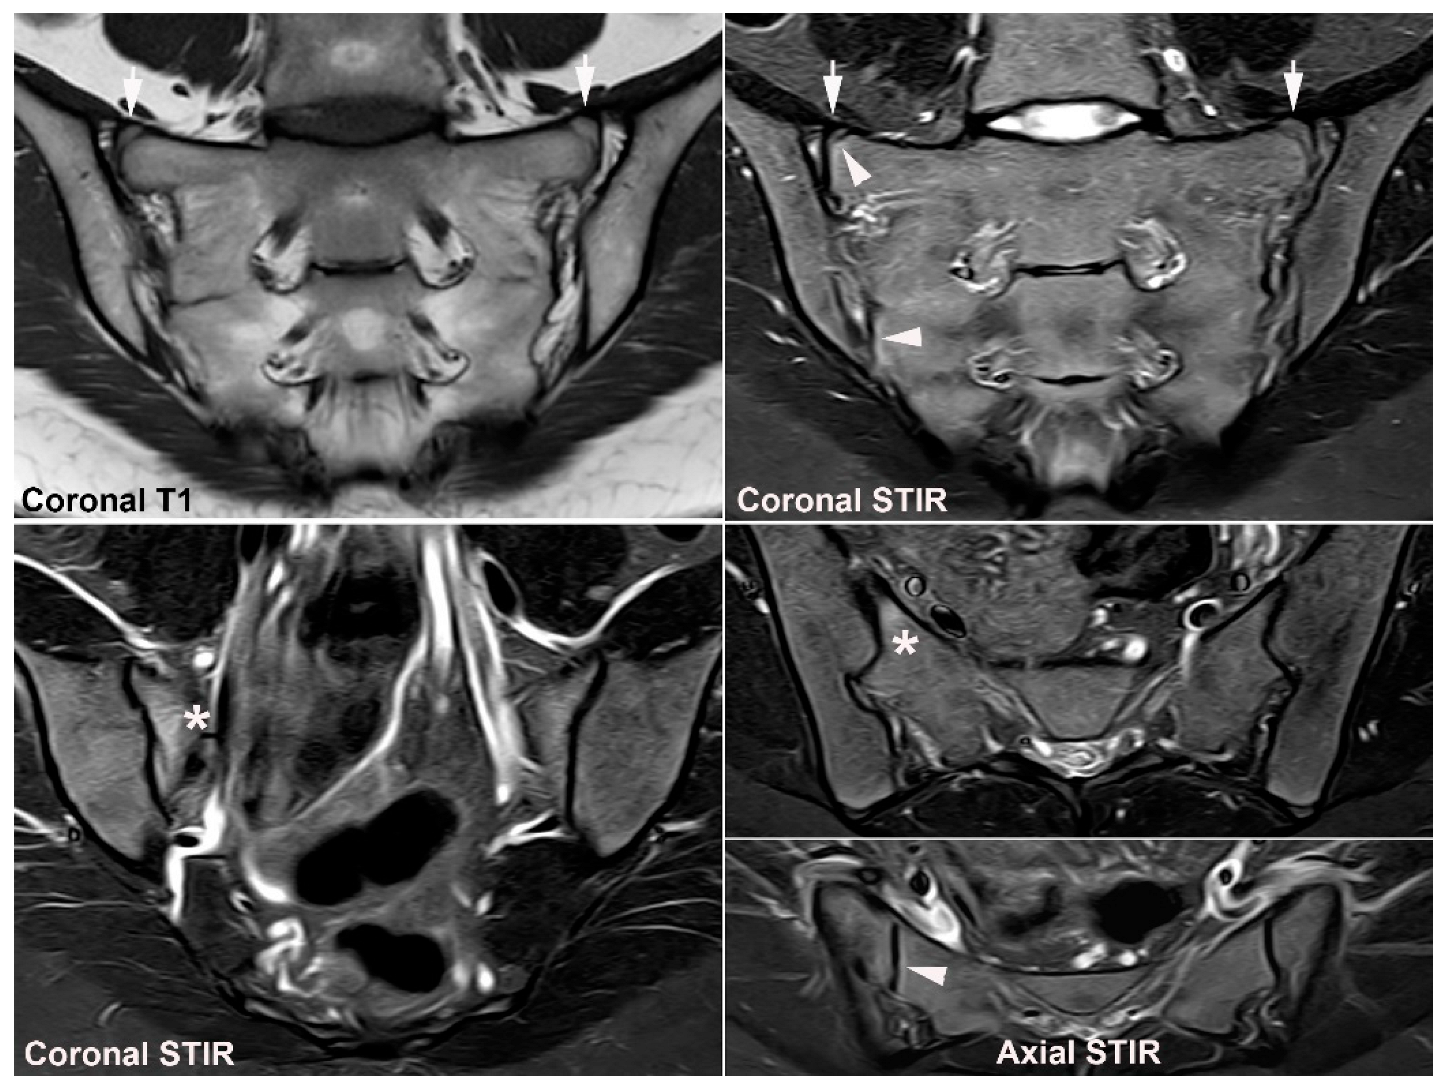

- Kiil, R.M.; Weber, U.; Loft, A.G.; Maimburg, R.D.; Jurik, A.G. Evolution of MRI Lesions at the Sacroiliac Joints during and after Pregnancy by Serial MRI from Gestational Week 20 to 12 Months Postpartum. Arthritis Rheumatol. 2023. accepted. [Google Scholar] [CrossRef]